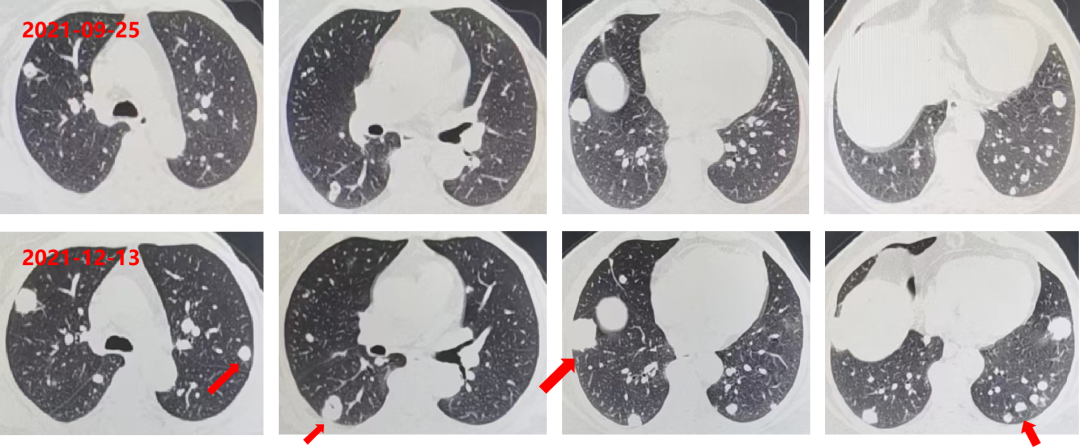

2021-09-25 复查CEA:82.1ng/ml。

胸部增强CT:双肺多发转移瘤,部分较前片增大;直肠壁增厚,较前稍减小;肝左叶低密度影,较前片变化不大。

肺内靶病灶稳定,出现新病灶,疗效评估PD。

2021-12-13 复查 CEA:165.9ng/ml。

胸部+全腹部增强CT:直肠壁增厚,较前未变化;肝左叶低密度影,较前片未变化;双肺多发转移瘤(靶病灶及非靶病灶增大)。

疗效评估PD。